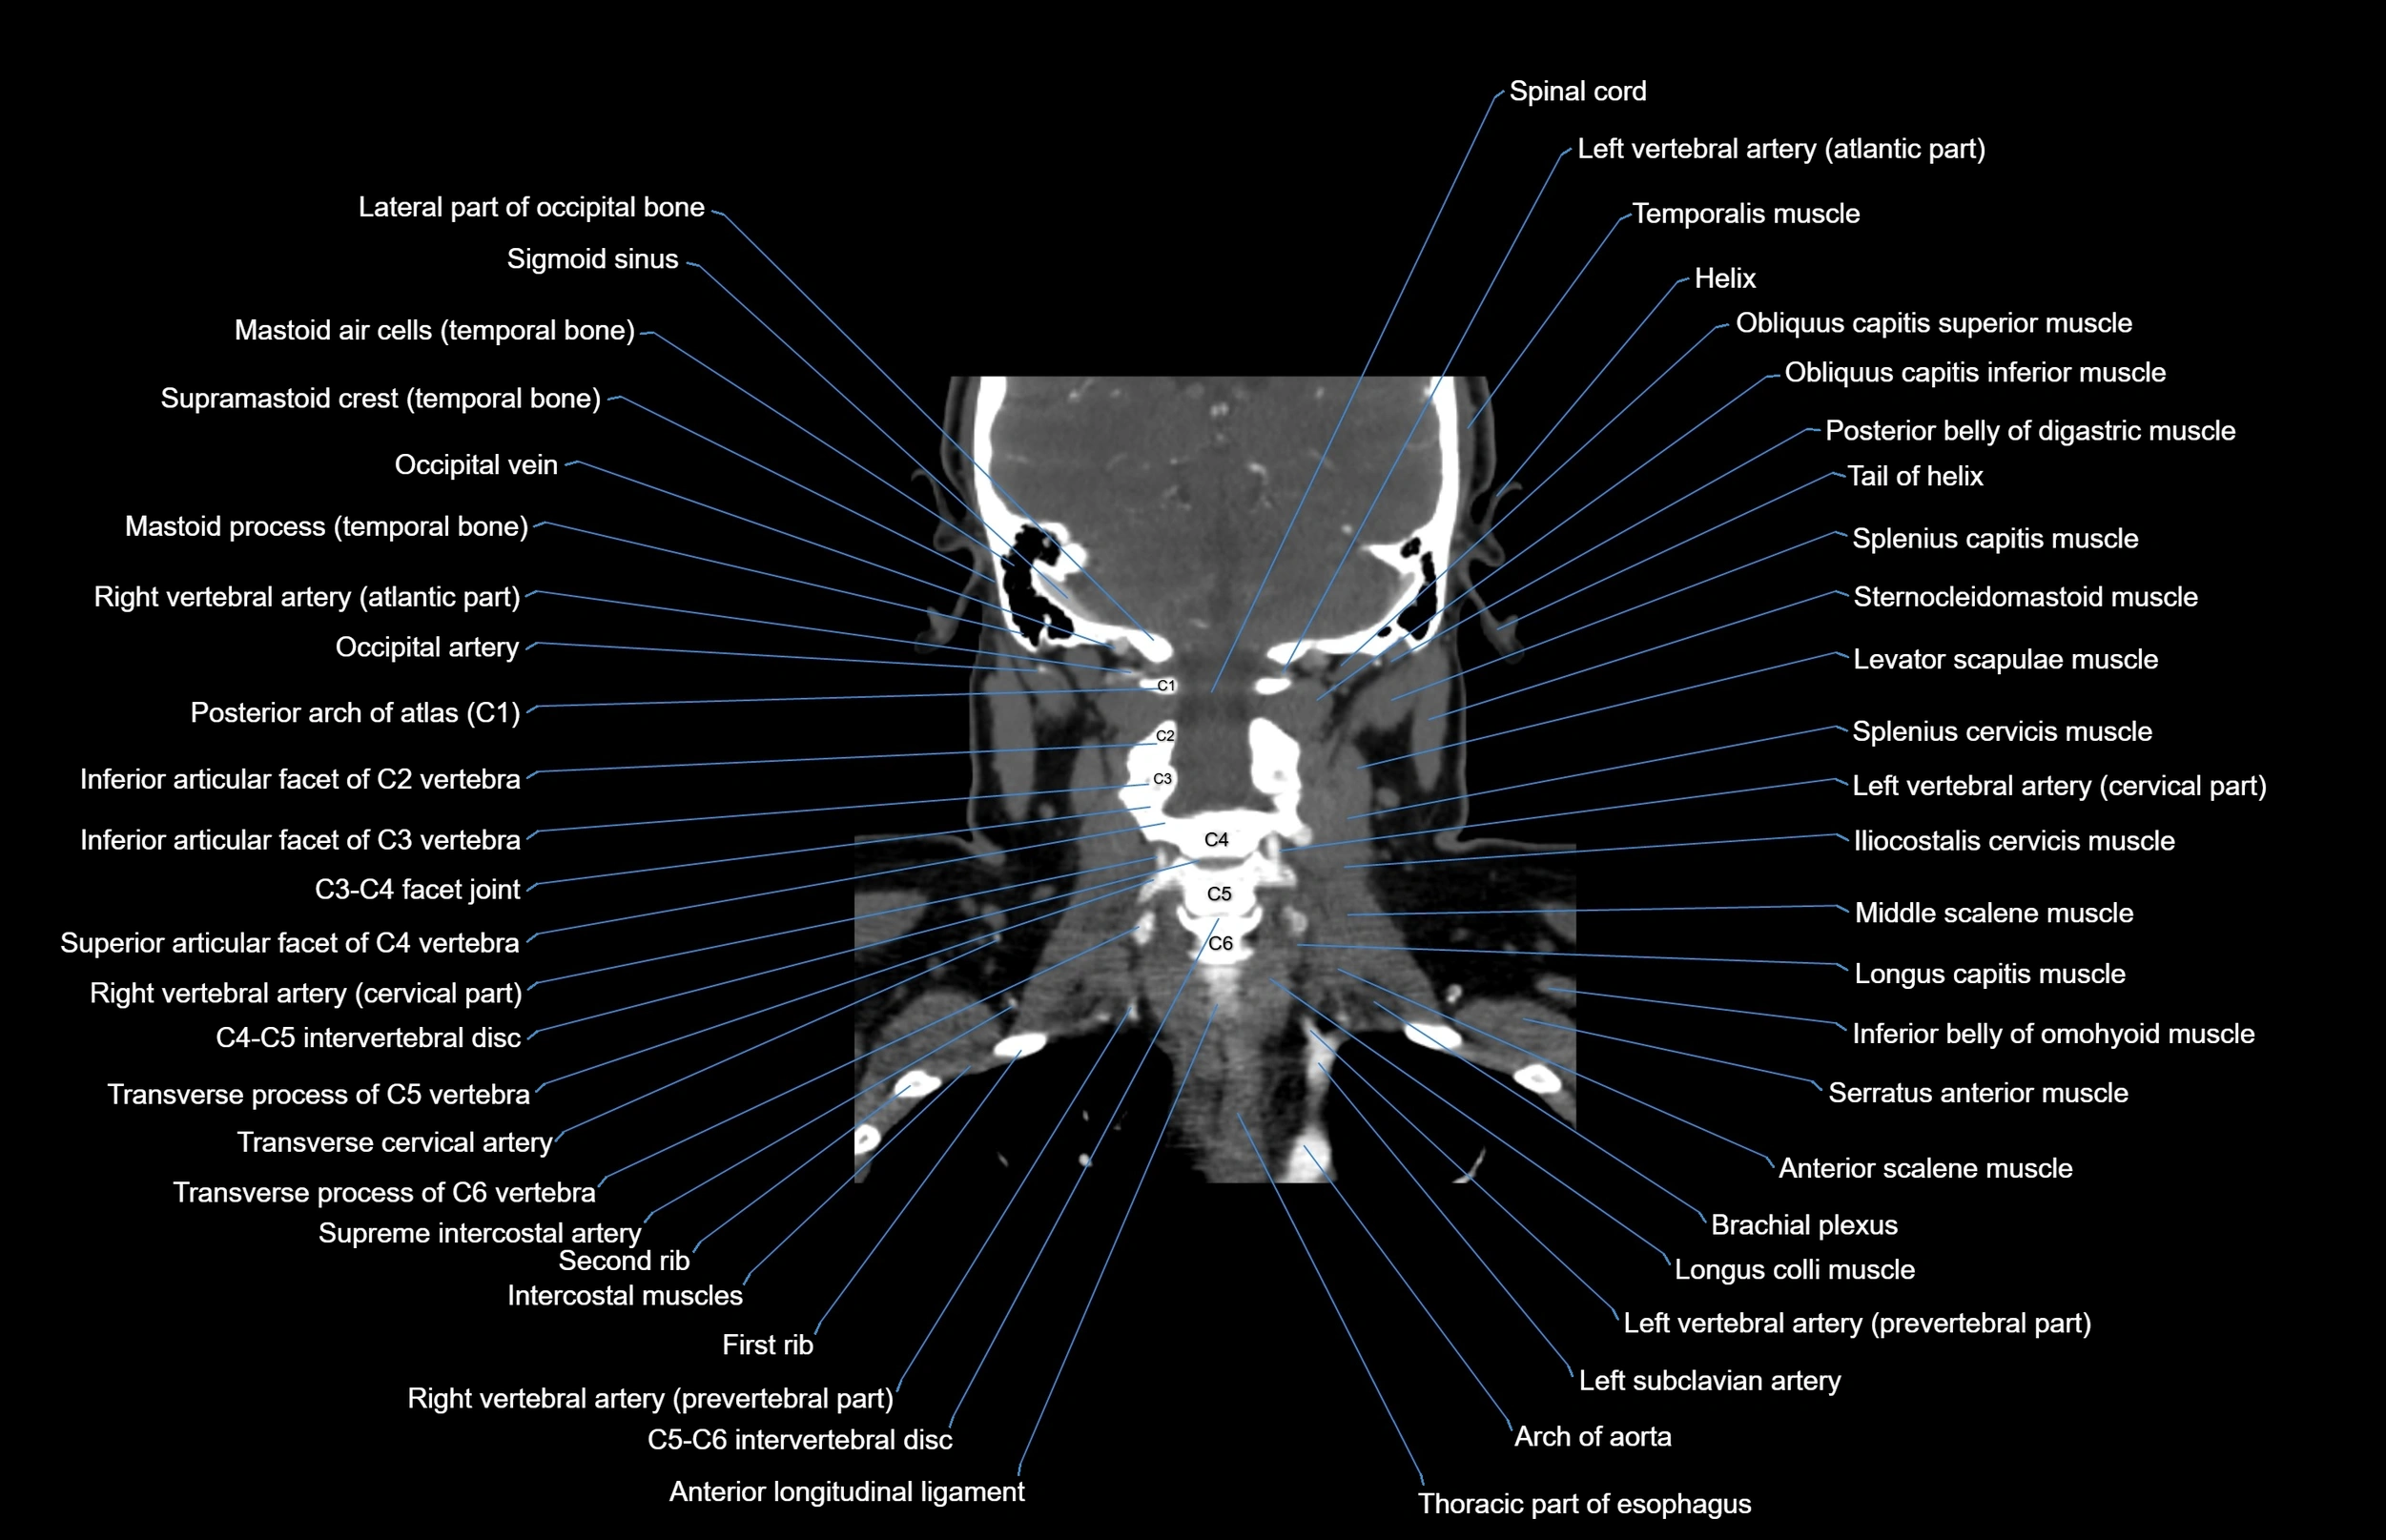

- Brachial plexus

- Iliocostalis cervicis muscle

- Left vertebral artery (atlantic part)

- Left vertebral artery (cervical part)

- Levator scapulae muscle

- Longissimus capitis muscle

- Obliquus superior capitis muscle

- Obliquus inferior capitis muscle

- Posterior arch of atlas

- Right subclavian artery

- Right vertebral artery

- Right vertebral artery (atlantic part)

- Right vertebral artery (cervical part)

- Serratus anterior muscle

- Spinal cord

- Splenius cervicis muscle

- Sternocleidomastoid muscle

- Thoracic part of esophagus